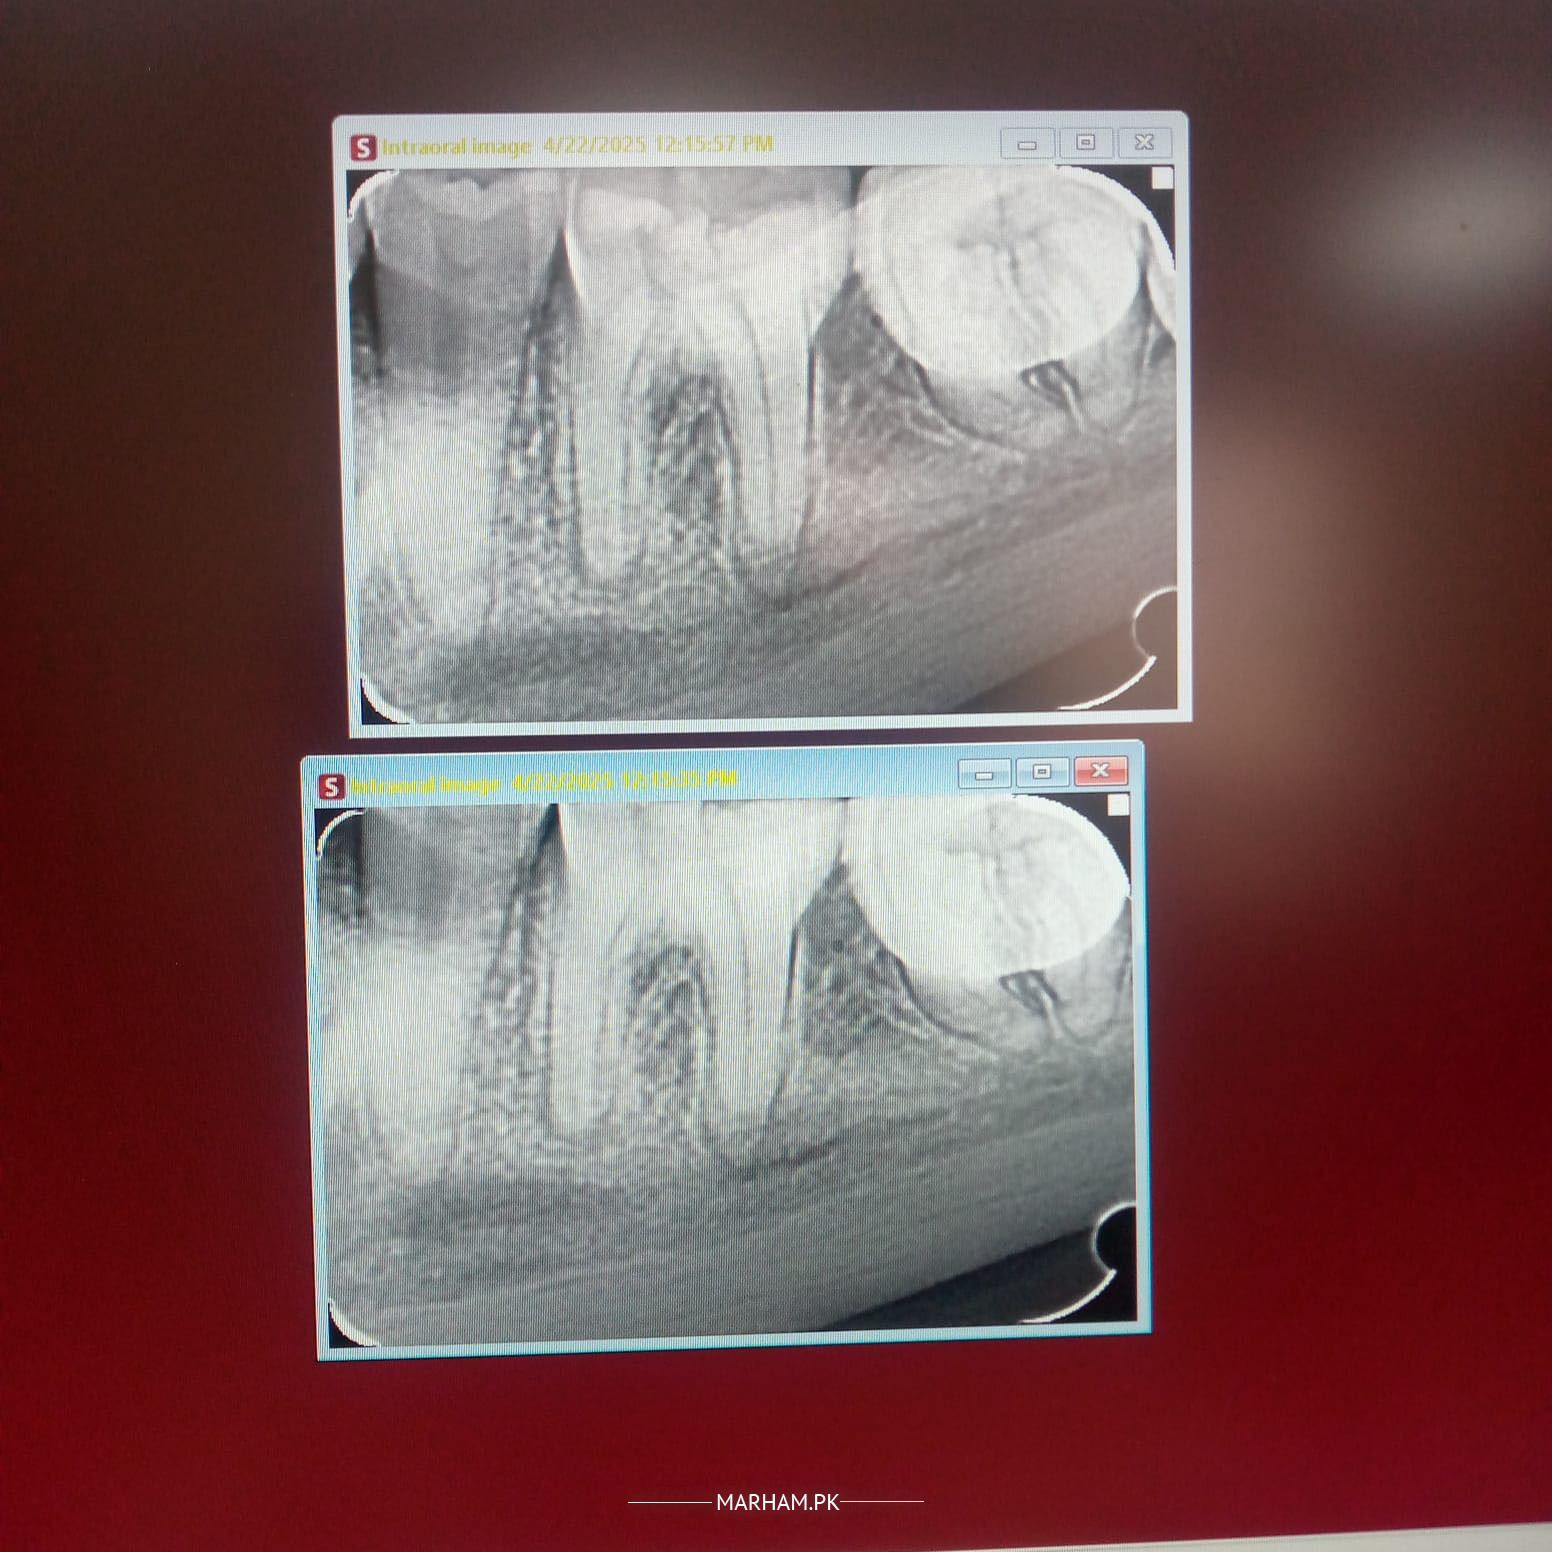

Darh main kaafi pain hai xray attach kar raha hoon kindly yeh bta dyn kiya eska treatment ho sakta hai ya darh nikalwani hogi ya dead krwani hogi?

RCT ho gee

yes treatment is possible

RCT (root canal treatment)

root canal might be possible but can only confirm after seeing clinically

Rct hoskati hai per clinically bhi dkehna hoga

yes treatment (RCT) is possible

Yes Rct hoskti ha lekin clinically dekhna parega Aqal darh ha ya USA pehla wali darh

Wisdom tooth hai or dard kate to zaroor nikalna chahiye